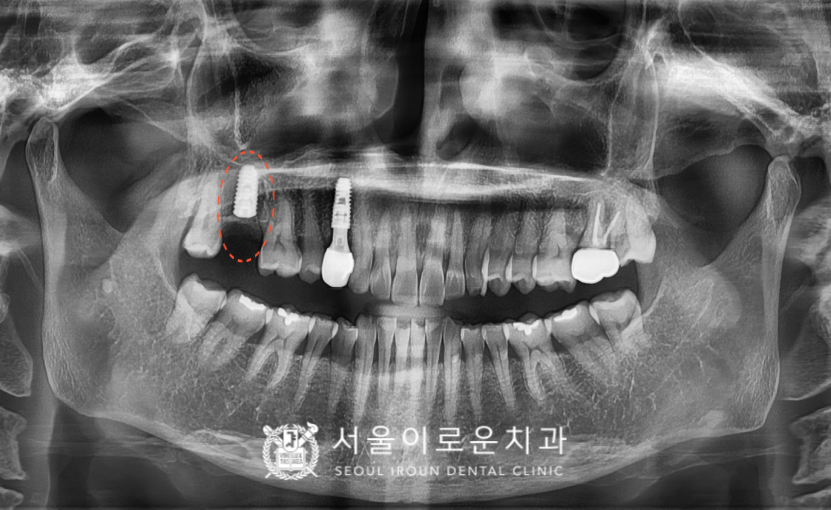

오른쪽 위 첫 번째 작은 어금니(#14)는

발치 후 염증조직을

깨끗하게 제거한 뒤

뼈이식을 동반하여

발치 후 즉시 식립을 도와드렸고,

임플란트와 뼈가

유착되길 기다리는 기간 동안

왼쪽 치경부 마모증 부위에

레진 수복을 진행해 드렸습니다.

그리고 임플란트 식립 후 2달 반 후에

뼈와 임플란트가 단단하게

결합이 잘 되었는지 확인하는

osstell beacon이라는 장비를 이용하여

골유착정도(isq)를 측정하였고,

안정 값을 확인한 뒤

보철 과정까지 마무리해 드렸습니다.